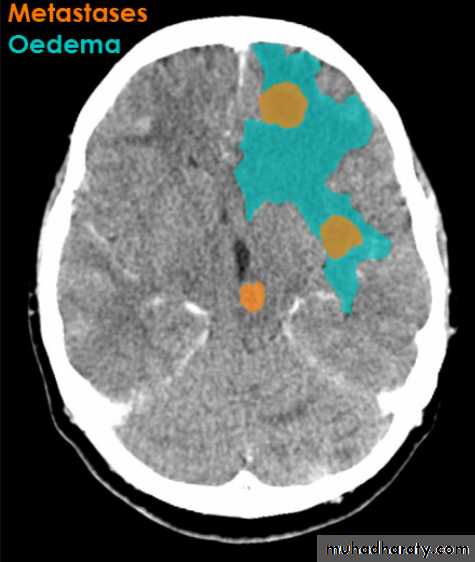

Secondary metastasis

Old age group above 50 Y , any lesion within the cerebellar hemisphere it is secondary metastasis unless proven otherwise F. from breast CA M. from bronchogenic CA .

Appear as nodular single or multiple lesion hypo dense or hyper dense .

Surrounded by per focal edema

Enhanced as solid or ring pattern of enhancement .